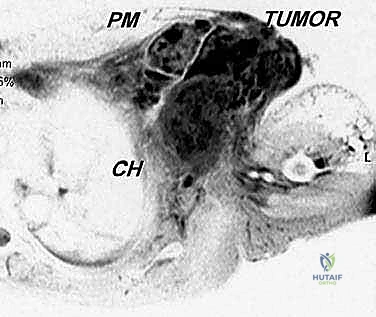

في حالة الأورام الخبيثة (مثل الساركوما)، يمتد الورم غالبًا عبر الحواجز العضلية ويغزو الضفيرة العضدية (شبكة الأعصاب التي تغذي الذراع) والأوعية الدموية تحت الترقوة. لضمان عدم ترك أي خلايا سرطانية (تحقيق هوامش جراحية سلبية)، يجب إزالة الكتف بالكامل كوحدة واحدة (En Bloc resection).

- التصوير الطبي المتقدم: استخدام الرنين المغناطيسي (MRI) لتقييم الأنسجة الرخوة، والأشعة المقطعية (CT scan) للصدر للبحث عن أي نقائل سرطانية (Metastasis)، والتصوير المقطعي بالإصدار البوزيتروني (PET Scan).